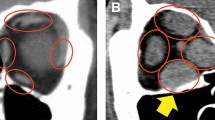

Extraocular muscles were analyzed with orbital images obtained using a whole-body CT system (SOMATOM Definition AS+; Siemens, Erlangen, Germany) without contrast. Axial scans were obtained at an angle of − 10° to − 15° to the orbitomeatal line, and coronal scans in a paraxial plane 90° to the orbital axis were reconstructed from the axial scans (slice thickness, 2 mm). We measured the diameter of all rectus muscles shown on six slices from the globe’s posterior margin to the orbital apex (Fig. 3). The maximum diameter was defined as the thickest diameter of each muscle on the six slices. The spindle-like spreading of the rectus muscles without tendon involvement was identified morphologically as EEM23. Diameters of the superior, inferior, medial, and lateral rectus muscles were measured on coronal scans. The inferior and superior oblique muscles were excluded because their course is oblique to the coronal plane.

Anatomically, the rectus muscles are typically 2.5–4.0 mm thick at the midpoint24. Therefore, we classified rectus muscles > 4.0 mm thick as enlarged. On this basis, this study involved 371 participants (199 patients with EEM and 172 controls with NEM). All 199 EEM patients were diagnosed with GO.

The coronal slice (a) and the result (b) used for the segmentation of the eyeball. The coronal slice (c) and the result (d) were used for the orbit segmentation. The coronal slice (e) and region of interest (the area inside the blue squares) (f) used when Residual Network-50 recognized the retrobulbar region from (b) and (d).